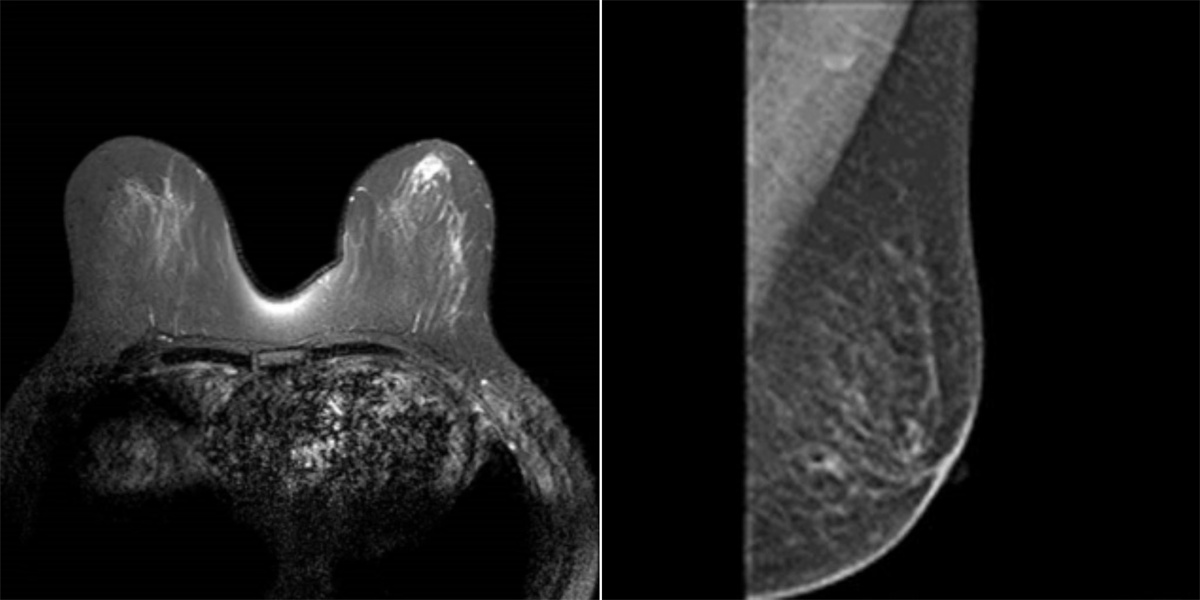

崔舜瑀教授带领团队在术前进行了充分的病情分析、术前切口的标记与测量,依照两位女士的意愿,为她们量身定制了个性化的手术方式和预案准备。术中,团队使用自制的“乳腺单孔腔内镜戳卡”进行操作,1例采用“逐层法”切除全部腺体并完整保留乳头乳晕。1例采用“逐层法”切除全部腺体及乳头乳晕,手术过程十分顺利。目前患者切口愈合良好,术区无任何异常,无不良反应及并发症,此术式在避免术后放疗的同时,兼顾健康和美观,且“无痕”,患者及家属表示非常满意,并顺利出院。

术后,崔舜瑀教授表示,该术式的主要亮点一是通过达芬奇机器人灵活的机器手及超清晰3D成像技术达到更精细的手术操作,既能解决肿瘤治疗又能最大限度减少损害,满足患者对健康和美的双重需求;二是应用前哨淋巴结活检切口施行单孔建腔使其切口更加隐蔽,解决了乳房表面切口带来的皮瓣坏死、积液等术后并发症的风险,规避了患者胀痛不适等缺点,实现了乳房表面无痕化的美容效果,而且保留胸大肌的功能不受影响,改善乳房形态。